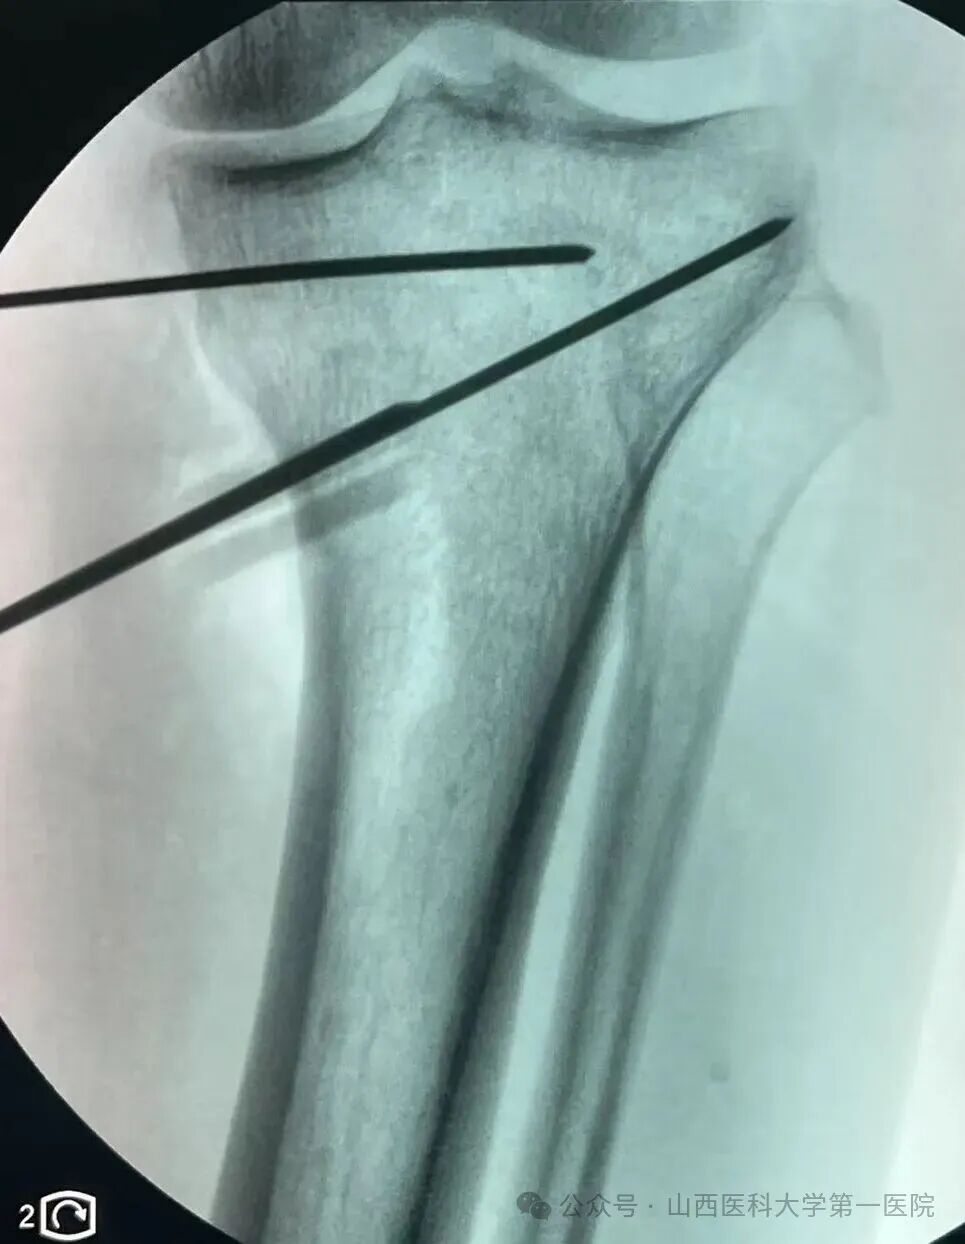

术中通过3D-PSI导板进行截骨